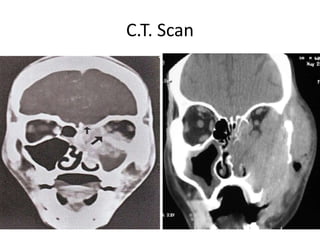

C.T. Scan Nose & Paranasal sinus: expansion & destruction of bony wall

C.T. Scan

Diagnostic nasal endoscopy C.T.Scan Nose & Paranasal sinus: expansion & destruction of bony wall Biopsy Diagnosis